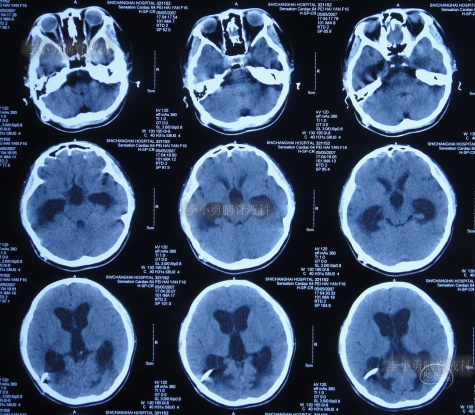

脑积水第1次脑室腹腔分流术后14年,即第2次脑室腹腔分流术后13年,即第3次脑室腹腔分流术后3个月半,5次就诊于给予手术的医院但仍脑积水,颅内感染情况下于2020年4月11日,住入李小勇脑脊液科,入院时:头晕伴视物不清,呕吐,睡眠差,头部有手术瘢痕(图-13);入院时头颅CT示脑积水,脑室内有3根管(图-14)。

图-13:2020年4月11日入院时

图-14:2020年4月11日入院时头颅CT

入院后4天即2020年4月15日,拔除了原3根分流管+两侧脑室外引流术(图-15)。

图-15:2020年4月15日头颅CT

图-16:2020年4月16日头颅CT

图-17:2020年4月16日

图-18:2020年4月19日

图-19:2020年4月19日头颅CT

入院治疗11天即2020年4月22日, 查头颅CT示脑室缩小,出血消失(图-20),头晕呕吐消失。

图-20:2020年4月22日头颅CT